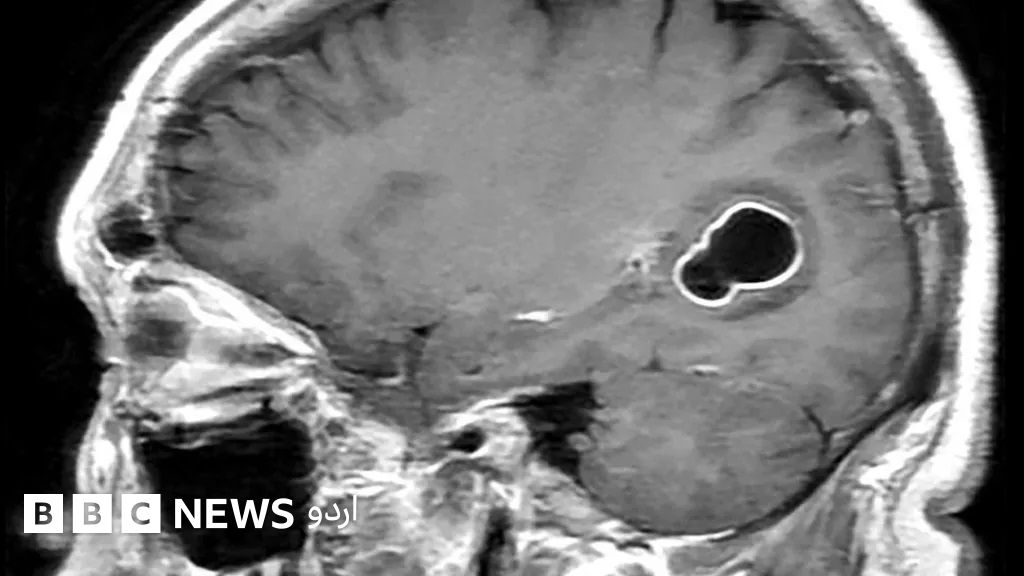

مسلسل سر کے درِد میں مبتلا ایک شخص کے دماغ میں ٹیپ وارم (پیٹ میں پائے جانے والے کیڑے) کا لاروا پاپا گیا ہے اور ڈاکٹروں کا کہنا ہے کہ ممکن ہے یہ سور کا کچا گوشت کھانے کی وجہ سے مریض کے دماغ میں داخل ہوا ہو۔

ڈاکٹروں نے انھیں دماغ کا سکین کروانے کا مشورہ دیا۔ سکین کیے جانے پر معلوم ہوا کہ اُن کے دماغ میں ٹیپ وارم (عموماً پیٹ میں پائے جانے والے کیڑے) کے لاروے کی موجودگی کے سبب ایک چھالا بن گیا تھا۔

امریکن سینٹر فار ڈیزیز کنٹرول اینڈ پریوینشن (سی ڈی سی) کے مطابق ٹیپ وارم لاروا پٹھوں اور دماغ جیسے ٹشوز میں داخل ہو جاتا ہے اور چھالے کی شکل اختیار کر لیتے ہیں۔ دماغ میں چھالا بن جانے کی حالت کو نیوروسیسٹی سرکوسس کہا جاتا ہے۔